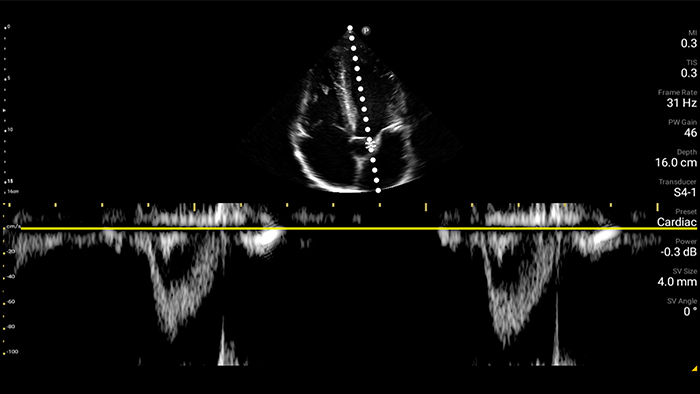

Lumify S4-1 broadband phased array transducer

• 4 to 1 MHz extended operating frequency range • 2D, color Doppler, M-mode, advanced XRES and multivariate harmonic imaging • High-resolution imaging for abdominal and cardiac applications: Cardiac, OB/GYN, Lung, Abdomen and FAST imaging preset optimizations

Case study

A patient with dyspnea

Pre-hospital point of care cardiac ultrasound: pulmonary embolism